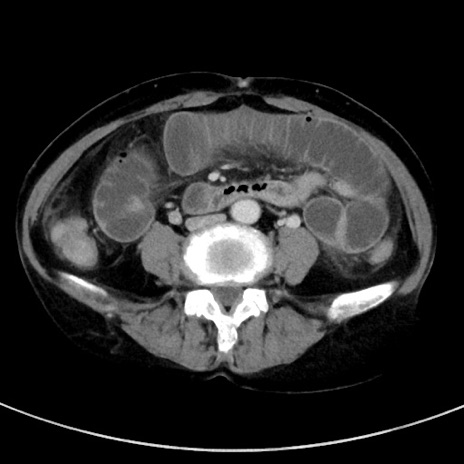

症例23(横断像)

【症例】70歳代女性

【主訴】下腹部痛・嘔吐

【現病歴】2日前より腹痛あり。昨日嘔吐あり。症状改善しないため来院。

【既往歴】胃GISTに対して胃部分切除後。

【身体所見】BT 37.1℃、BP 128/77mmHg、腹部:平坦・軟、下腹部に圧痛あり。

【データ】WBC 10200、CRP 0.31